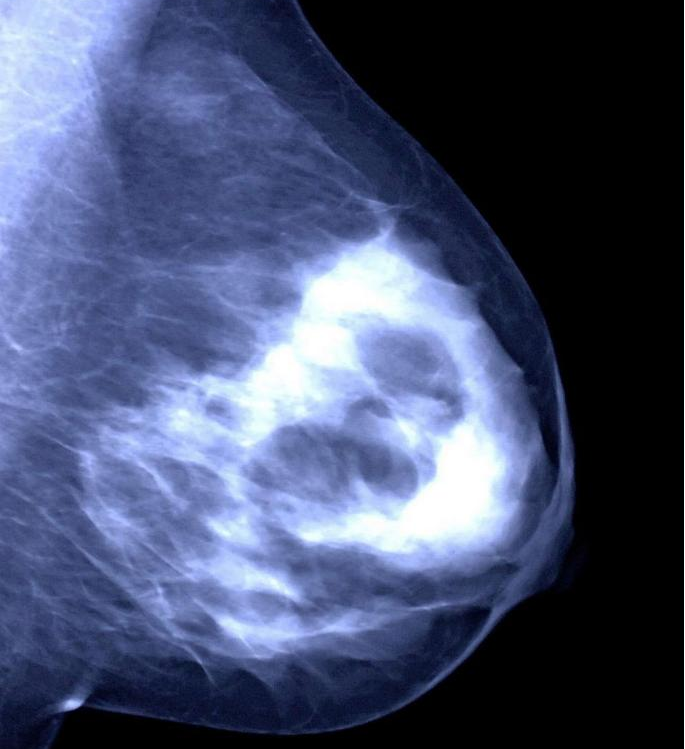

②乳腺钼靶:有点像给乳房拍“X 光片”,能发现一些超声看不到的细小钙化,对40岁以上女性筛查乳腺癌很有帮助。

③病理活检:如果怀疑肿物有问题,医生会取一点肿物组织做检查,这是判断肿物良恶性的“金标准”,就像给肿物做“身份鉴定”一样。